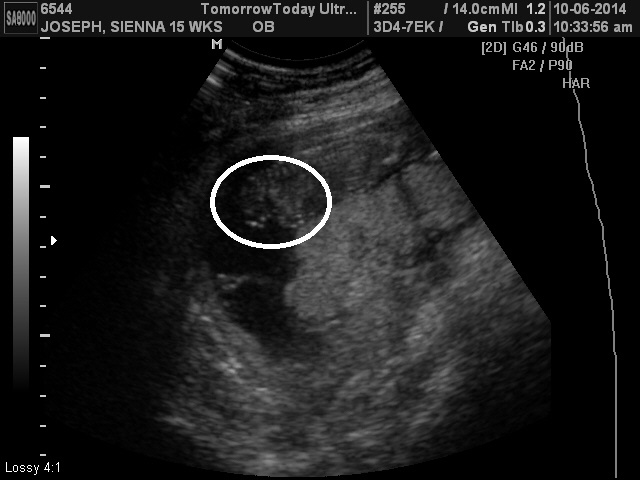

The second picture I was told was of the genitalia. They look like feet!

I'm confused. I was told I need to come back in Saturday because my gender pictures were taken incorrectly and are invalid.